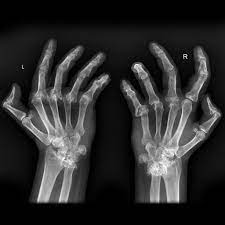

If the pattern of disease is not symmetrical, then a different diagnosis should be considered. Imaging tests you may get. The 2010 rheumatoid arthritis classification criteria help doctors diagnose rheumatoid arthritis. The ulnar styloid is destroyed with the rest of the distal ulna (white arrow), there is destruction of the carpal bones (yellow arrow) and there is dislocation of the 1st metacarpal on the destroyed trapezium. It can affect anyone of any age. Rheumatoid arthritis (ra) is a chronic autoimmune multisystemic inflammatory disease that affects many organs but predominantly attacks the synovial tissues and joints. Rheumatoid arthritis affects around 400,000 adults aged 16 and over in the uk. Rheumatoid arthritis can be difficult to diagnose because many conditions cause joint stiffness and inflammation and there's no definitive test for the condition. Ra causes pain, swelling, stiffness, and loss of function in joints. Rheumatoid arthritis is an inflammatory arthritis affecting both small and large joints in a symmetric distribution. Rheumatoid arthritis is an immune system condition, or autoimmune disorder, that causes inflammation of the lining of the joints. Rheumatoid arthritis is a chronic inflammatory disorder that can affect more than just your joints. Rheumatoid arthritis manifests as a symmetrical arthritis, most commonly affecting the hands.

If the pattern of disease is not symmetrical, then a different diagnosis should be considered. In rheumatoid arthritis, the body's immune system attacks its own healthy cells inside certain joints, leading to an inflammatory response. For more information and past images of the month, go to. However, they are not useful in the early stages of rheumatoid arthritis, before joint damage occurs. </b>rheumatoid arthritis (ra) is a polyarticular disease with bilateral and symmetric distribution. Sorptiometry should be performed to diagnose. The rheumatoid community on reddit. Rheumatoid arthritis (present for >10 years). The ulnar styloid is destroyed with the rest of the distal ulna (white arrow), there is destruction of the carpal bones (yellow arrow) and there is dislocation of the 1st metacarpal on the destroyed trapezium. Rheumatoid arthritis affects around 400,000 adults aged 16 and over in the uk. Reddit gives you the best of the internet in one place. Ra causes pain, swelling, stiffness, and loss of function in joints. The earliest manifestation of rheumatoid arthritis of the forefoot is synovitis of the mtp joints with eventual hyperextension deformity of the mtp joints including distal.